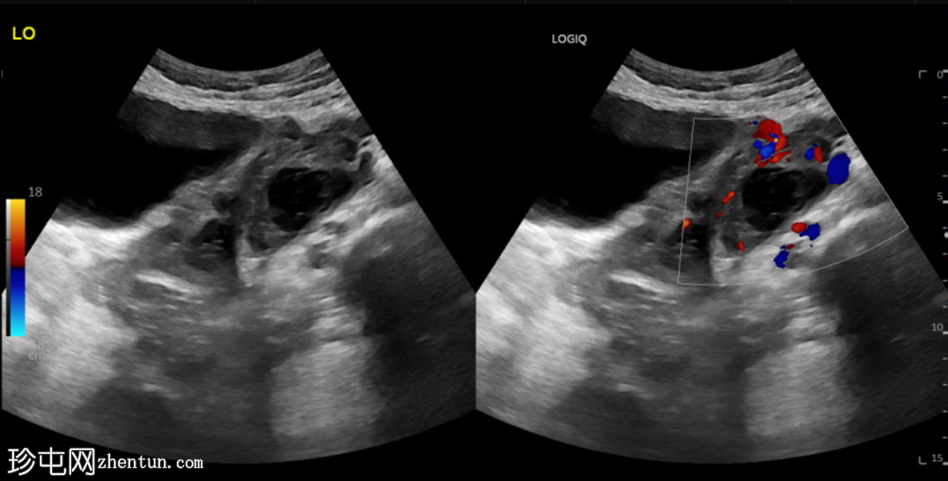

横切面

左侧卵巢明显增大,可见一囊肿,大小约3.2 x 2.3 cm,呈火环征,可能为黄体囊肿。左侧卵巢与子宫之间可见一管状结构,直径约1.3 cm,内含浑浊液体,未见血管,最可能为输卵管积血。以上特征提示可能为左侧异位妊娠。

未见宫内妊娠囊。